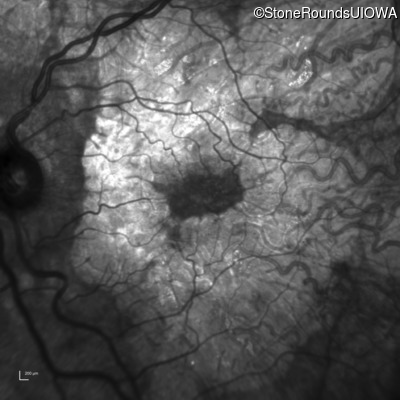

AR Stargardt Disease (IIA)

Age at visit: 51 years

This 51 year old woman first experienced some abnormality in her distance vision when she was 27 years old. She feels that her vision has been stable since that time.

Diagnosis & molecular findings

Disease Gene Allele 1 variant(s) Allele 2 variant(s) Inheritance mode

AR Stargardt Disease ABCA4 Gly1507Arg GGG>AGG IVS42+1 G>A AR